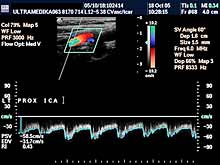

A) Krvni sudovi vrata

Vrsta i sadržaj pregleda:

- Pregled velikih krvnih sudova vrata CD i CPA

modom (obavezno karotidnih i vertebralnih arterija celim tokom).

Pregled podrazumeva procenu ukupne debljine krvnih sudova (indirektna

procena koronarne bolesti), procenu stepena suženja, karakteristika aterosklerotičnog plaka, procena hemodinamike i postavljanje

indikacija za operativno lečenje.

Primenjena tehnika:

- Sono CT,

- XRes,

- 2D Broad band,

- Broad band - CD,

- CPA ,

- CPD.

Preporučeni pregledi:

- nakon 45. godine starosti,

- obavezno ako postoje

faktori rizika

(hipertenzija, pušenje, stres, poremećaj nivoa masti u

krvi, kod sumnje da postoji koronarna bolest),

- kontrola na 6-12

meseci.